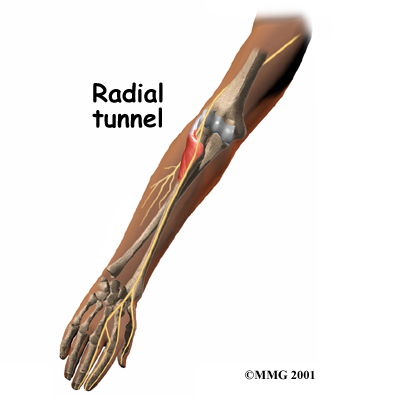

On the lateral part of the elbow, the radial nerve enters a tunnel formed by muscles and bone. This is called the .

Passing through the radial tunnel, the radial nerve runs below the . The supinator muscle lets you twist your right hand clockwise. This is the motion of using a screwdriver to tighten a screw.

After the radial nerve passes under the supinator muscle, it branches out and attaches to the muscles on the back of the forearm.